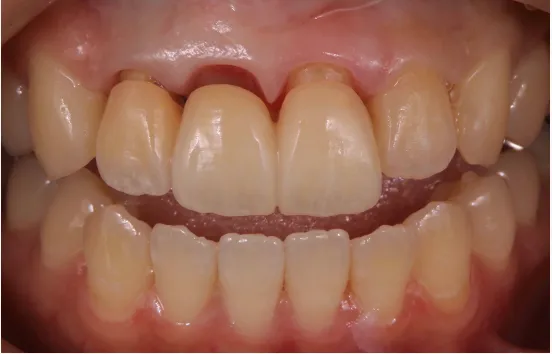

当院では、歯茎が黒い事が原因で、人前で笑えず、悩まれ、常に口元を押さえながら話をしなけばならない方など多くのご相談を頂きます。

特に前歯の差し歯などが黒くなってしまっていると目立ちやすいため、その悩みは深刻です。

以前、前歯の差し歯の変色と歯茎が黒くなってしまっている患者様の治療を行いました。

人と話す時は、常に口元に手を当て見えないように隠し、人前で笑うことも少なくなってしまったと仰っていました。

たった一本の差し歯ですが、ご本人からすると笑顔を見せられず、大変苦労されてきたことと思います。

治療後には、自然と笑う回数が増え、今では口元を手で隠すこともなくなりました。

歯の自信が内面の自信に繋がることを強く感じさせられた瞬間でした。

1本の差し歯で人生が変わる事だってあります。